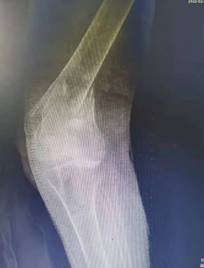

经X片等检查,王娭毑被诊断为左侧股骨远端粉碎性骨折,被收入骨科二十一病室(创伤外科)住院治疗。